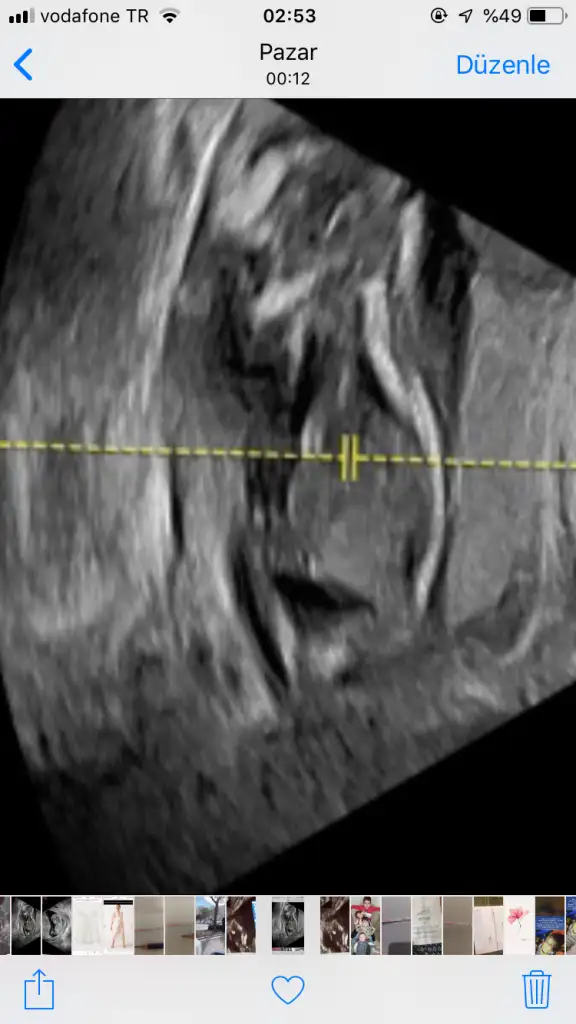

Hngisiymiş pipiKizlar beni bile tereddutte biraktirdiniz cinsiyet konusunda aksam aksam ultrasyon resmine baktimdegisirmi bilemiyorum artik ayrintiliya daha var doktor pipisi bu dedi sag tarafa bakin

Hngisiymiş pipianlamadım çizsene

Orası baban kafasının yanında kolları gibi geldi ama doktor dediyse doğrudur

Kiz kafasi obur taraftaOrası baban kafasının yanında kolları gibi geldi ama doktor dediyse doğrudur

Kiz kafasi obur taraftabu alt bolumu bacak arasiymis orasi degisirmi dedim bak simdi burda gorunen degisirmi dedi. Bilemedim artik

yav ben anlayamıyorum bende kafa popo net sadece yüzüstü böle görünce anlamıyom ozaman doğrudur